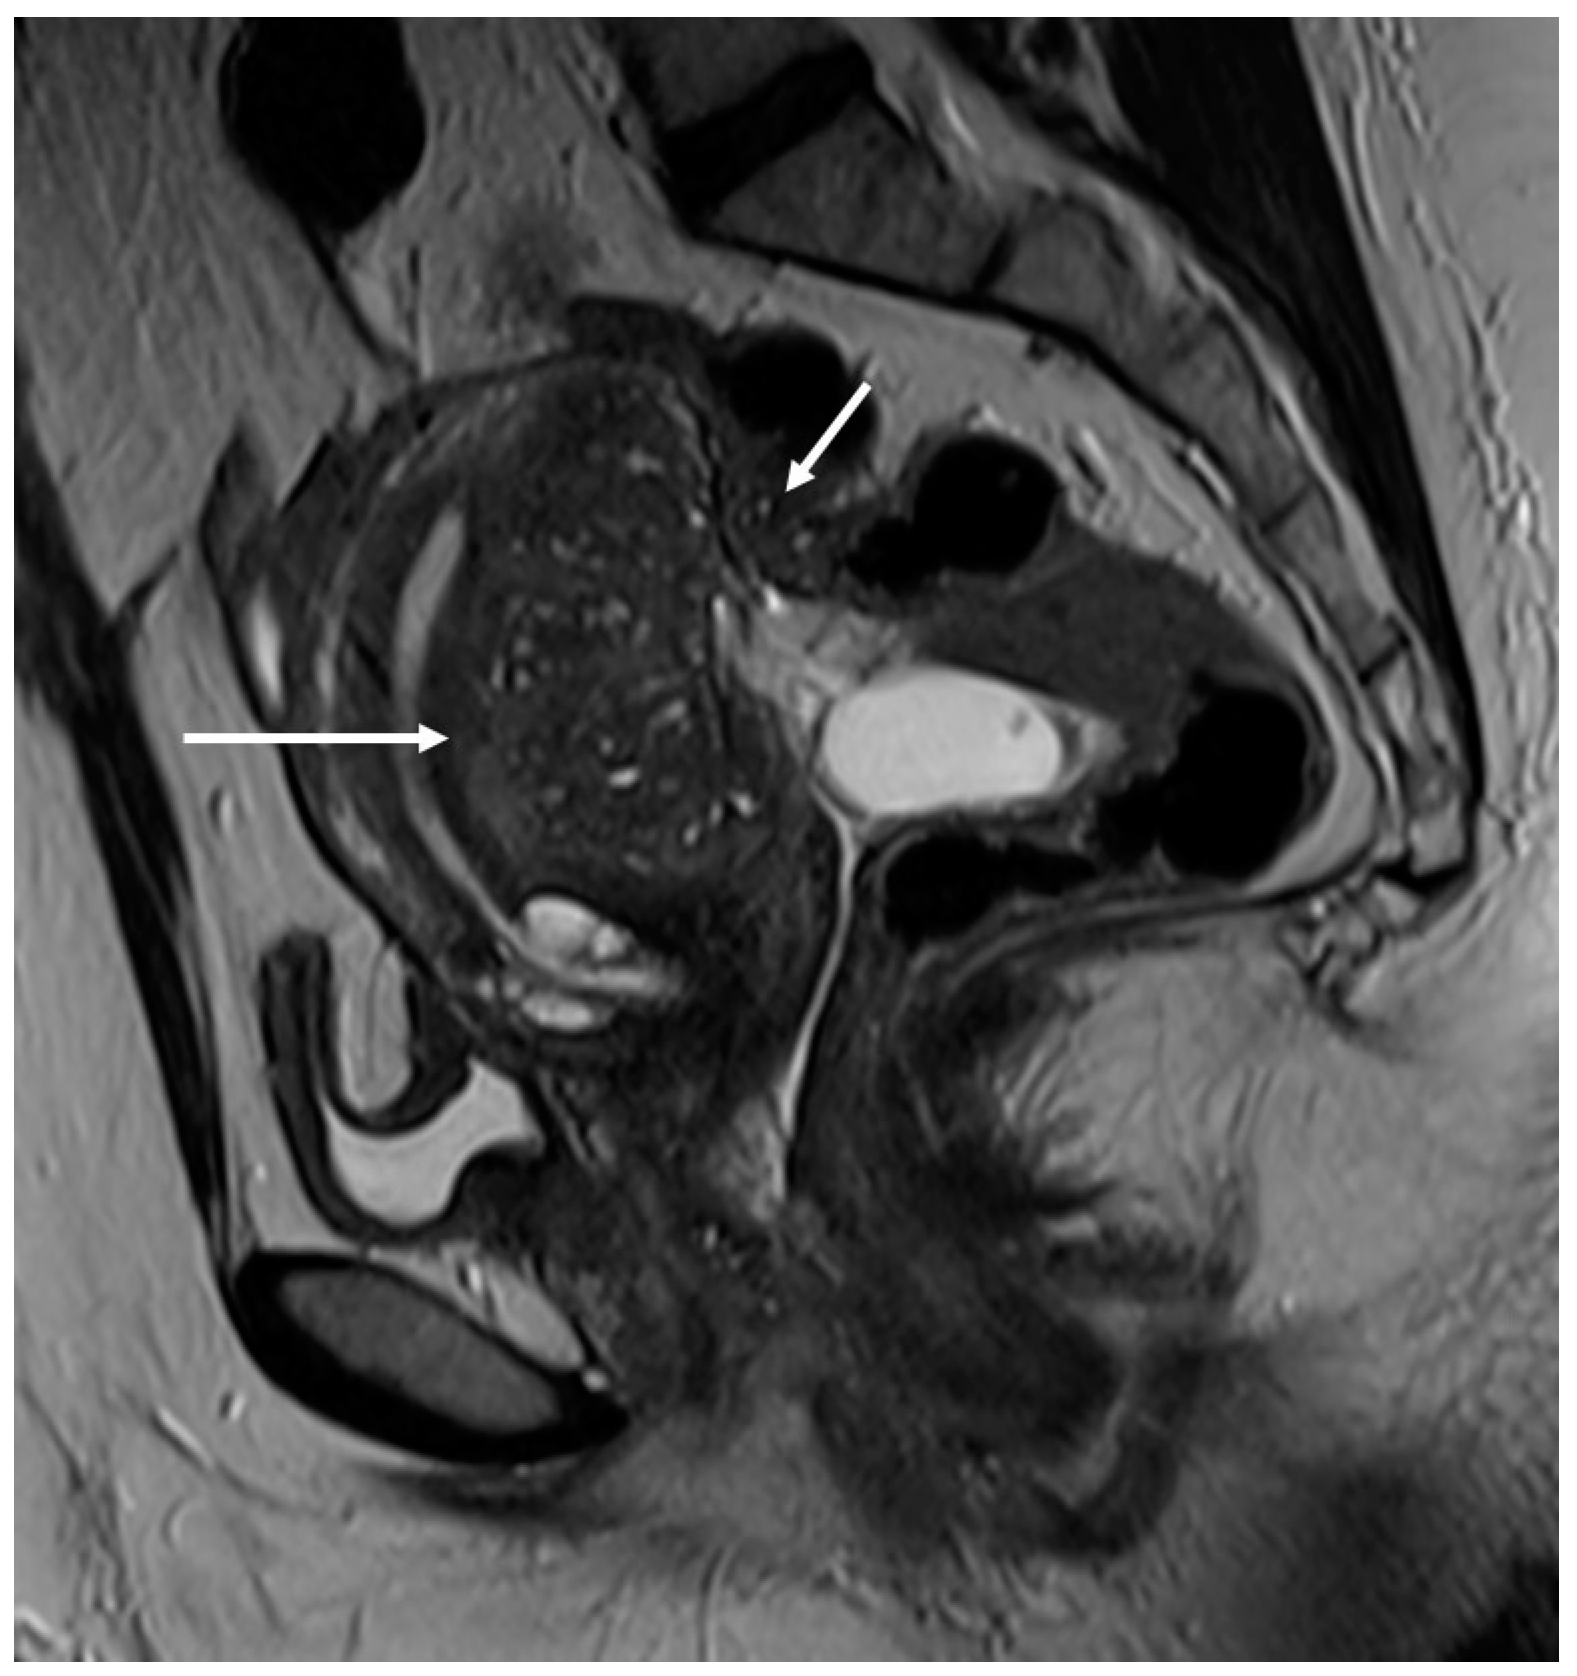

In order to perform a correct evaluation, the bladder must be at a degree of repletion suitable for the correct study of its walls and its lumen: those nodules or masses are responsible for the loss of the normal hypointense signal of the muscularis layer on T2WI. Hemorrhagic content may also be seen as hyperintense foci on T1WI, and it is also possible to observe hyperintense cystic areas on T2WI [7,14] (Figure 1).

Figure 1.

Localization of endometriosis in the vesico-uterine pouch in a 42-year-old female. (A) Sagittal T2WI (black arrow); (B) Sagittal fat-suppressed T1WI (white arrow); (C) Coronal T2WI (black arrow).

In the case of a mural mass protruding into the lumen, mucosal or submucosal edema is well depicted on T2WI [40].